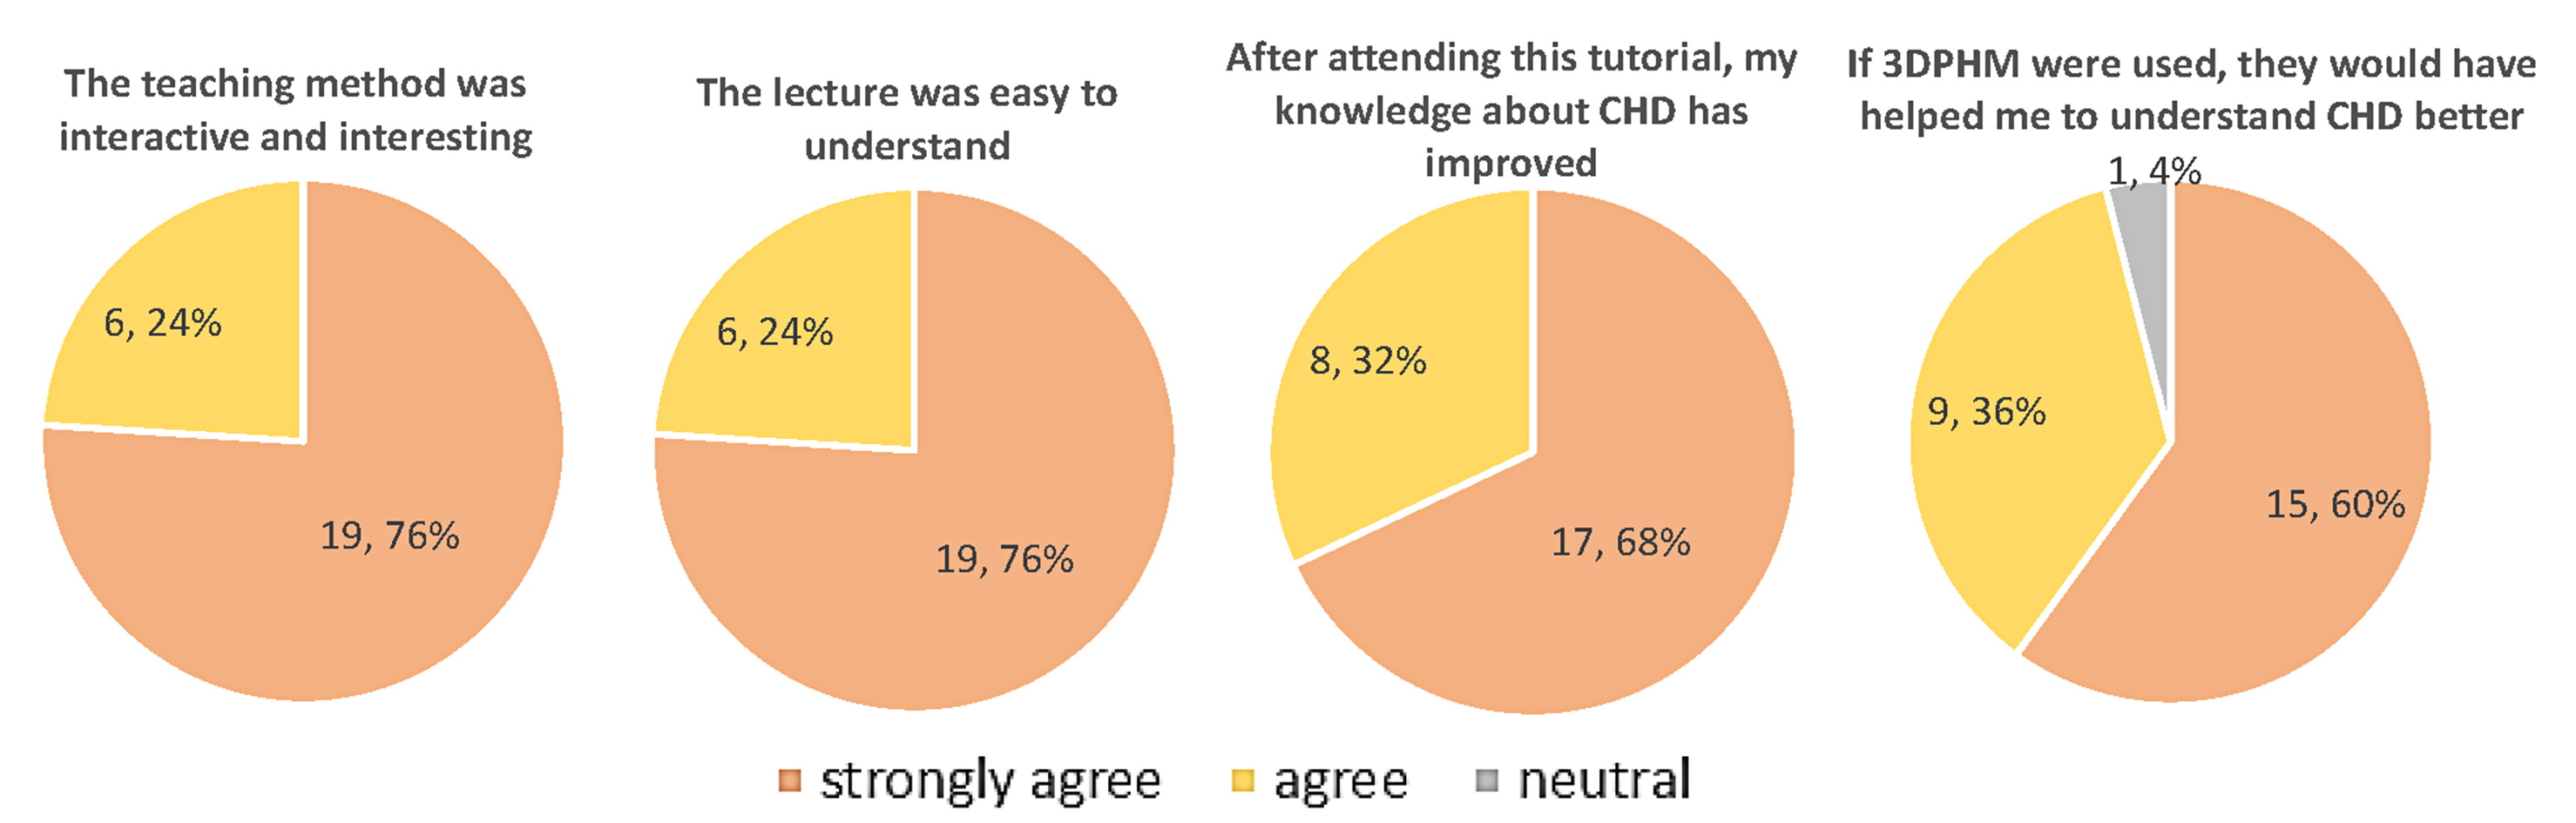

In comparing survey responses between the control and 3DPHM groups, the Mann-Whitney U test showed no significant difference in all of the questions. Figs. 7,8 illustrate the survey responses in percentage for the control group and 3DPHM group, respectively. Both groups of students indicated either ‘strongly agree’ or ‘agree’ that the teaching method was interactive and interesting (U = 346.5, p = 0.93). Slightly more students in 3DPHM group indicated ‘strongly agree’ that the education was easy to understand (82%) compared to the control group (76%), although this is not statistically significant (U = 331.5, p = 0.64). More students in 3DPHM indicated ‘strongly agree’ that their knowledge about CHD has improved (86%) compared to the control group (68%), and again this is not statistically significant (U = 292, p = 0.16). About 64% of the students in 3DPHM group indicated ‘strongly agree’ that the 3DPHM played an important role in helping them understand CHD. This is similar to the control group where 60% indicated ‘strongly agree’ that the 3DPHM would help them to understand CHD (U = 349.5, p = 0.99). However, one student in the 3DPHM group disagreed that the 3DPHM helped in his/her learning of CHD.

Fig. 7.

Fig. 7.Survey responses (number of students, percentage) of the control group with regards to the education session. 3DPHM, three-dimensional printed heart model; CHD, congenital heart disease.

As for the survey responses, although not statistically significant, greater percentage of students in 3DPHM group responded that the lecture was easy to understand, and that their knowledge on the topic of CHD has improved. In Loke et al.’s [2] study, the 3DPHM group rated significantly higher satisfaction score towards the teaching session, when compared to the control group. On the other hand, a meta-analysis found that the 3DPHM is associated with higher subjective evaluation scores and satisfactory level among the study participants [9]. This is also reflected in our study in which majority of the students responded (96% in the control group and 85% in the 3DPHM group) ‘agree’ or ‘strongly agree’ that the 3DPHM had helped them to gain a deeper understanding of CHD. Hence, the 3DPHM has contributed to improving students’ learning experience.